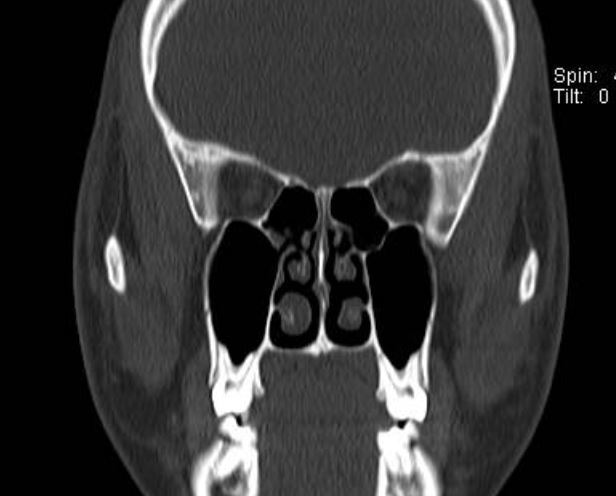

做了鼻内镜和鼻窦CT检查后发现主要的问题是下鼻甲肥大,堵塞了鼻腔。这种情况如果药物治疗效果不好,通过鼻内镜微创手术是可以解决的。